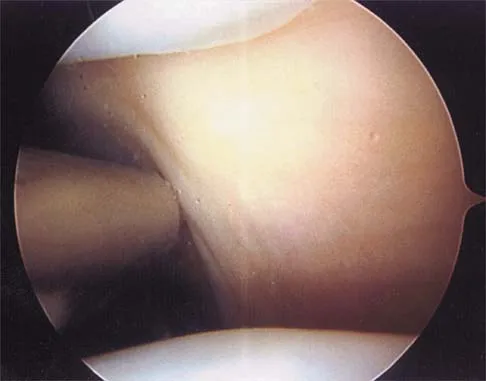

Figure 19 shows an arthroscopic view from the anterior lateral portal of the knee looking into the suprapatella pouch. The use of an electrothermal device during this procedure most commonly causes significant postoperative complications by damaging which of the following structures?